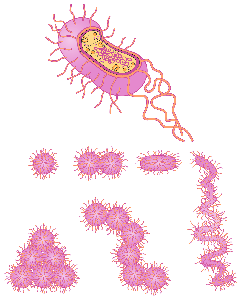

Detailreiche Fotografien aus der medizinischen Praxis ergänzen die Texte; moderne, genaue,

wissenschaftliche Zeichnungen geben Einblick in die Anatomie und die Funktion der Lunge und

anderer Organe.